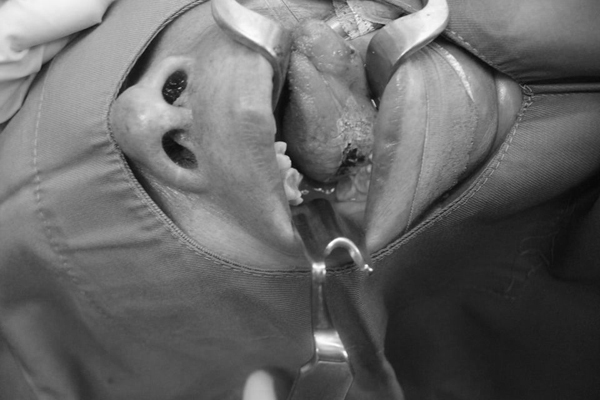

Ekip phẫu thuật cho bệnh nhân

Trực tiếp phẫu thuật cho bệnh nhân, PGS.TS Lê Minh Kỳ, khoa Khám bệnh theo yêu cầu và quốc tế - Bệnh viện E cho biết, tưa là một dạng nhiễm nấm ở miệng, thường mềm hơn và dễ chảy máu hơn so với bạch sản.

Hầu hết những nốt bạch sản có thể tự khỏi nhưng nếu có khối sùi bắt buộc đến bệnh viện để can thiệp phẫu thuật. Với khối kích cỡ nhỏ có thể cắt hớt bằng laser hoặc dao mổ. Tuy nhiên nếu kết quả sinh thiết sau mổ là ung thư thì phải phẫu thuật cắt bỏ vùng rộng để ngăn chặn lan truyền.